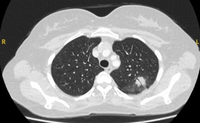

Cortes de tomografia computadorizada (TC) com exemplos de nódulos solitários semissólidos

Do acervo de Dr. George Tsaknis, MD, PhD, FRCP (Londres), MRQA, MAcadMEd, PGCert; usado com permissão